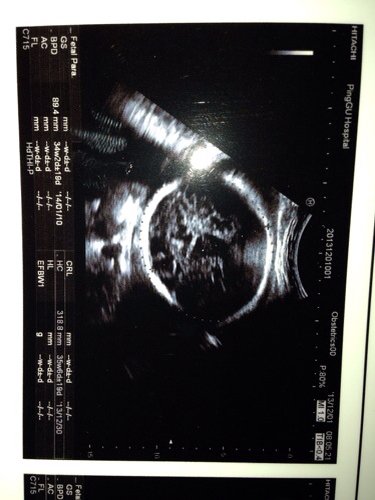

我怀孕34周两天,检查缺铁性贫血,怕孩子早产,不知道正常不正常,还说孩子头大,腿短 点击展开 匿名用户 2013-12-02 01:01 为您推荐: 其他回答 病情分析: 由于每个医院的实验设备,试剂不同,正常参考值也有一定的差异, 指导意见: 你的检查结果,建议咨询你的经治医生。祝你好孕。 六飞烟_TKY4 2013-12-02 09:52 相关问题 我怀孕34+2,今天检查医生说孩子头大,腿短,我还缺铁性贫血,我怕早产,我24周岁!想咨询孩子怎么 怀孕33周 股骨长径58mm 医生说会比正常人腿短点 这个严重吗? 怀孕17周+2 有缺铁性贫血可以吃复方阿胶桨吗?